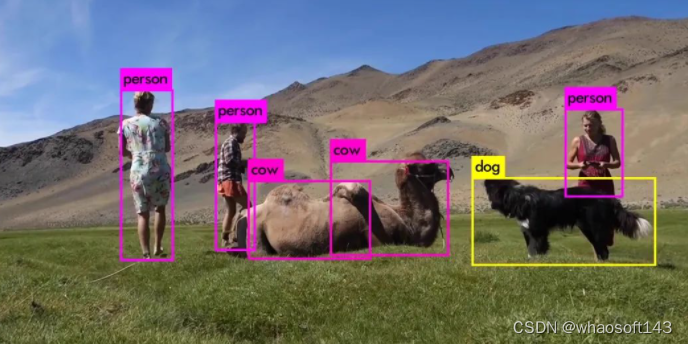

ADA-YOLO 模型针对医学影像中的多目标检测,解决了物体遮挡或截断等在医学影像中常见的挑战性问题。如图 4 所示,提出的检测方法可以成功检测到任何大小的红细胞缺失,与基准相比是一个很大的改进。ADA-YOLO 在所有类别中具有 0.918 的召回率,优于基准。

结果展示了 ADA-YOLO 在医学目标检测中揭示更多阳性实例的能力。通过更准确地识别出更高的真实阳性病例比例,即使存在遮挡,作者的模型也能显著提高疾病检测,减少诊断错误,并可以转化为更早、更准确的诊断。

与此同时,除了卓越的定量性能外,ADA-YOLO 在内存使用方面也非常高效。为了证明这一点,主要实验已经进行,并显示 YOLOv8 模型预测所有样本需要 26.9 MB 的内存和 35.1 GFLOPs 的计算能力,而作者的方法只需要 8.7MB 的内存,比 YOLOv8 节省了 3 倍的内存,并仅计算了 9.4 GFLOPs。

作者的模型在内存使用方面的出色效率是精心设计和优化的结果。通过有策略地实现紧凑而强大的架构特征,作者可以预期该模型在便携式医疗设备、边缘计算环境和资源受限的医疗设置中的实际应用,最终提高高级医学影像分析的可用性和负担能力。